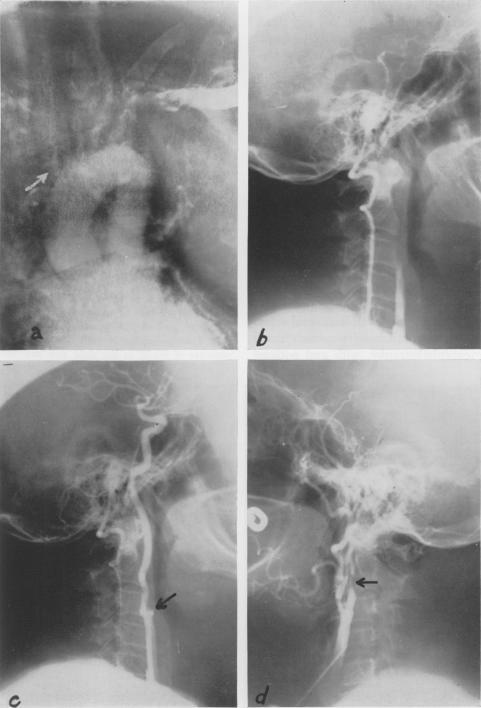

Critical evaluation and surgical correction of obstruction of obstruction in the branches of the aortic arch.

Ann Surg. 1960 Sep;152(3):472-84. doi: 10.1097/00000658-196009000-00010.